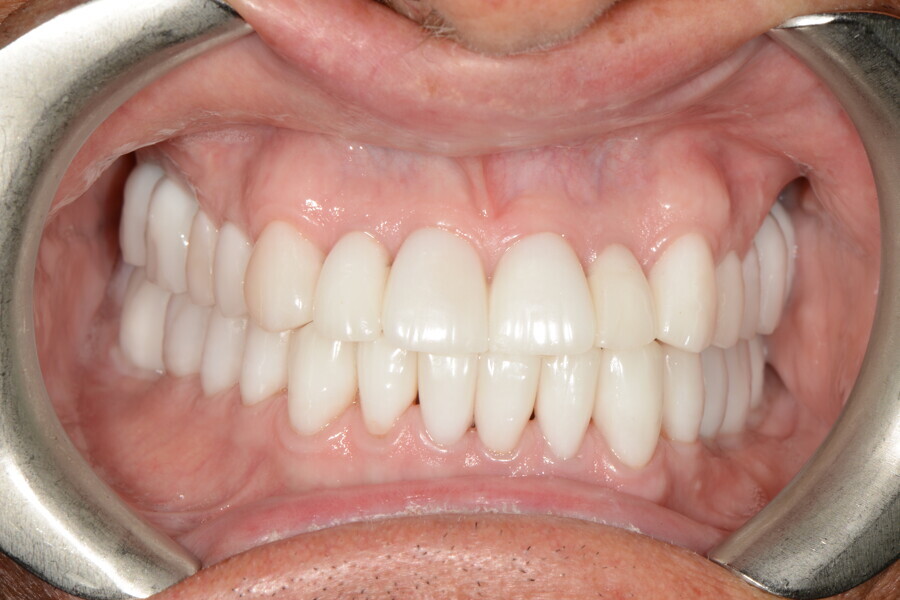

After the first phase of aligner treatment, we had achieved better inter-arch coherence, better maxillary arch expansion, and some space for improving the anterior tooth proportions restoratively (Fig. 19). We then temporarily restored the anterior teeth directly with composite, closing the spaces, improving the tooth proportions and further increasing the maxillary arch expansion (Fig. 20). We used restorative arch expansion to reduce the orthodontic destabilisation of the teeth to achieve the correct inter-arch coherence and retain the teeth in the cortical bone.38 A refinement aligner phase was undertaken to improve the final alignment of the gingival zenith and to improve the inter-arch coherence (Fig. 21). The periods of the first orthodontic phase and of the refinement were used to augment the mandibular and maxillary bone and to place the implants (Fig. 22). At the end of the orthodontic treatment, the case was finalised with ceramic veneers in the anterior area and temporary restorations on the implants in the posterior area (Figs. 23–26).

The provisional phase of about four months was important to allow the peri-implant tissue to mature and to teach the patient to chew correctly with chewing gum, cotton rolls and silicone masticatory sticks. This is fundamental training for the patient to achieve the correct alternating unilateral masticatory cycle needed to obtain the ideal rehabilitation of the masticatory system. We wanted the patient to achieve ideal masticatory and swallowing function. After sufficient rehabilitation time, we finalised the case with posterior zirconia crowns screwed on to the implants (Fig. 27).26

Our ideal final rehabilitation goals were:

• posterior stability;

• inter-arch coherence and U-shaped arches;

• anterior freedom during mastication;

• minimum disclusion vertical dimension;

• alternating unilateral masticatory cycle;

• physiological swallowing and high tongue posture against the palate; and

• mandibular disclusion advancing the mandible freely.

For maintenance purposes, after prosthetic finalisation, the patient was to carry on with the Froggymouth therapy and to use the Ri.P.A.Ra. for physiotherapeutic exercises and mastication training (Fig. 28). It was strongly recommended that the patient wear a mandibular occlusal splint during sleep. This occlusal splint was designed with disclusion guides to advance the mandible and ensure balanced contralateral support (Fig. 29).11, 39 We achieved an aesthetic appearance with adequate inter-arch coherence and a better cephalometric result (Figs. 30 & 31).